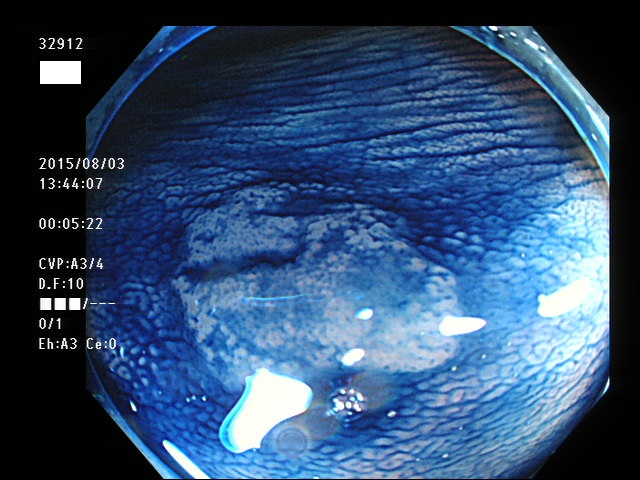

上記100名より抽出した平坦・陥凹型腺腫(=癌化の危険が高いが見落としやすい病変)の内視鏡写真